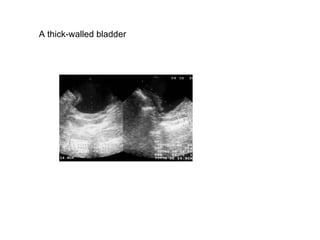

A thick-walled bladder

Tuberculosis. The bladder is thick walled and of  small volume.  The patient felt that the bladder was  full at the time of this scan